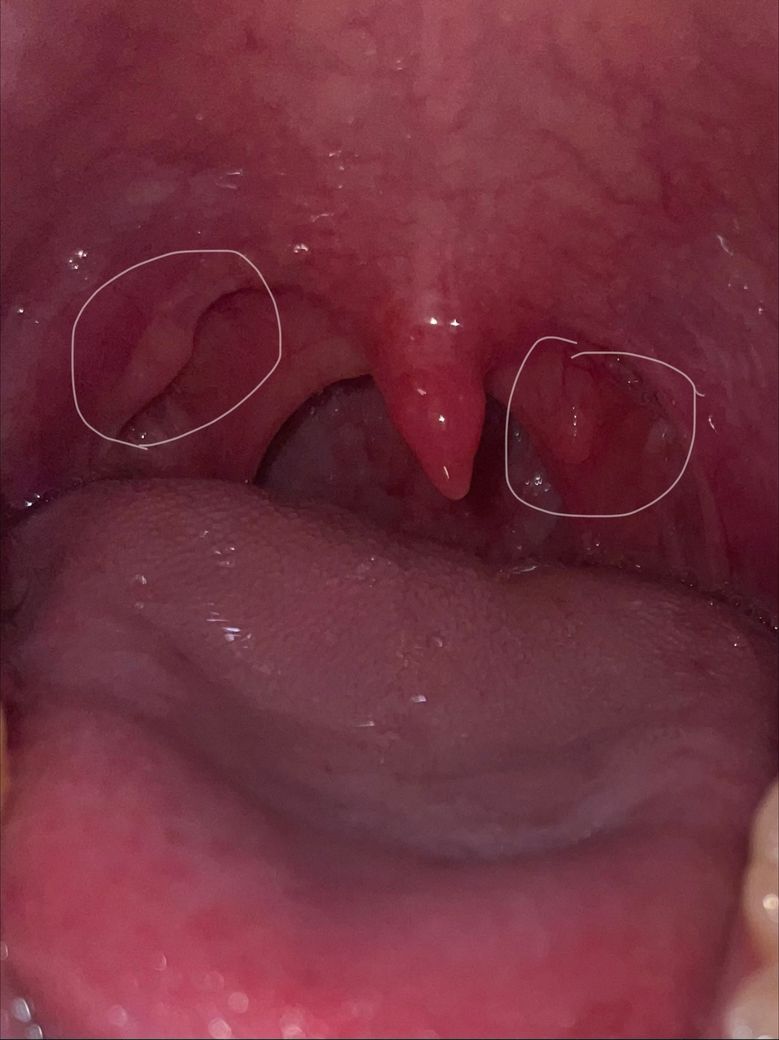

편도결석은 아닌 것 같고 사진 기준 목젖 오른쪽에 만져지는 혹 같은 게 있습니다

왼쪽에도 뭔가 볼록한 게 있는데 얘네 뭔가 문제되는 건가요? 병원가봐야하는 건가요 아프진 않습니다 만진 손의 냄새도 맡아봤는데 아무 냄새도 안 나요 뭐죠 이거

• 사진상 보이는 양측의 볼록한 구조는 위치와 형태상 편도기둥(구개궁)과 편도 주변 림프조직으로 보이며, 병적인 종괴라기보다는 정상 해부학적 구조 또는 경미한 림프조직 비대 가능성이 높습니다. 좌우가 비교적 대칭이고, 표면이 매끈하며 궤양이나 백색 삼출물이 없는 점은 악성이나 급성 감염 가능성을 낮추는 소견입니다.